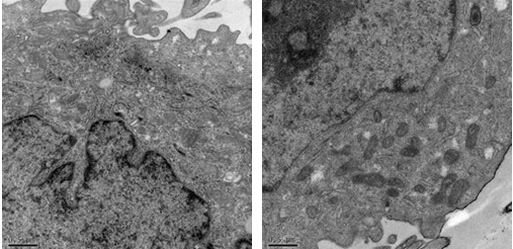

利用电子射线(或称电子束)穿透样品,而后经多级电子放大后成像于荧光屏。透射率高,可以用来观察组织和细胞

内部的超微结构以及微生物和生物大分子的全貌。能分辨0.1纳米以下的微细物质结构,放大倍数可达100万余倍。

结果示意图: